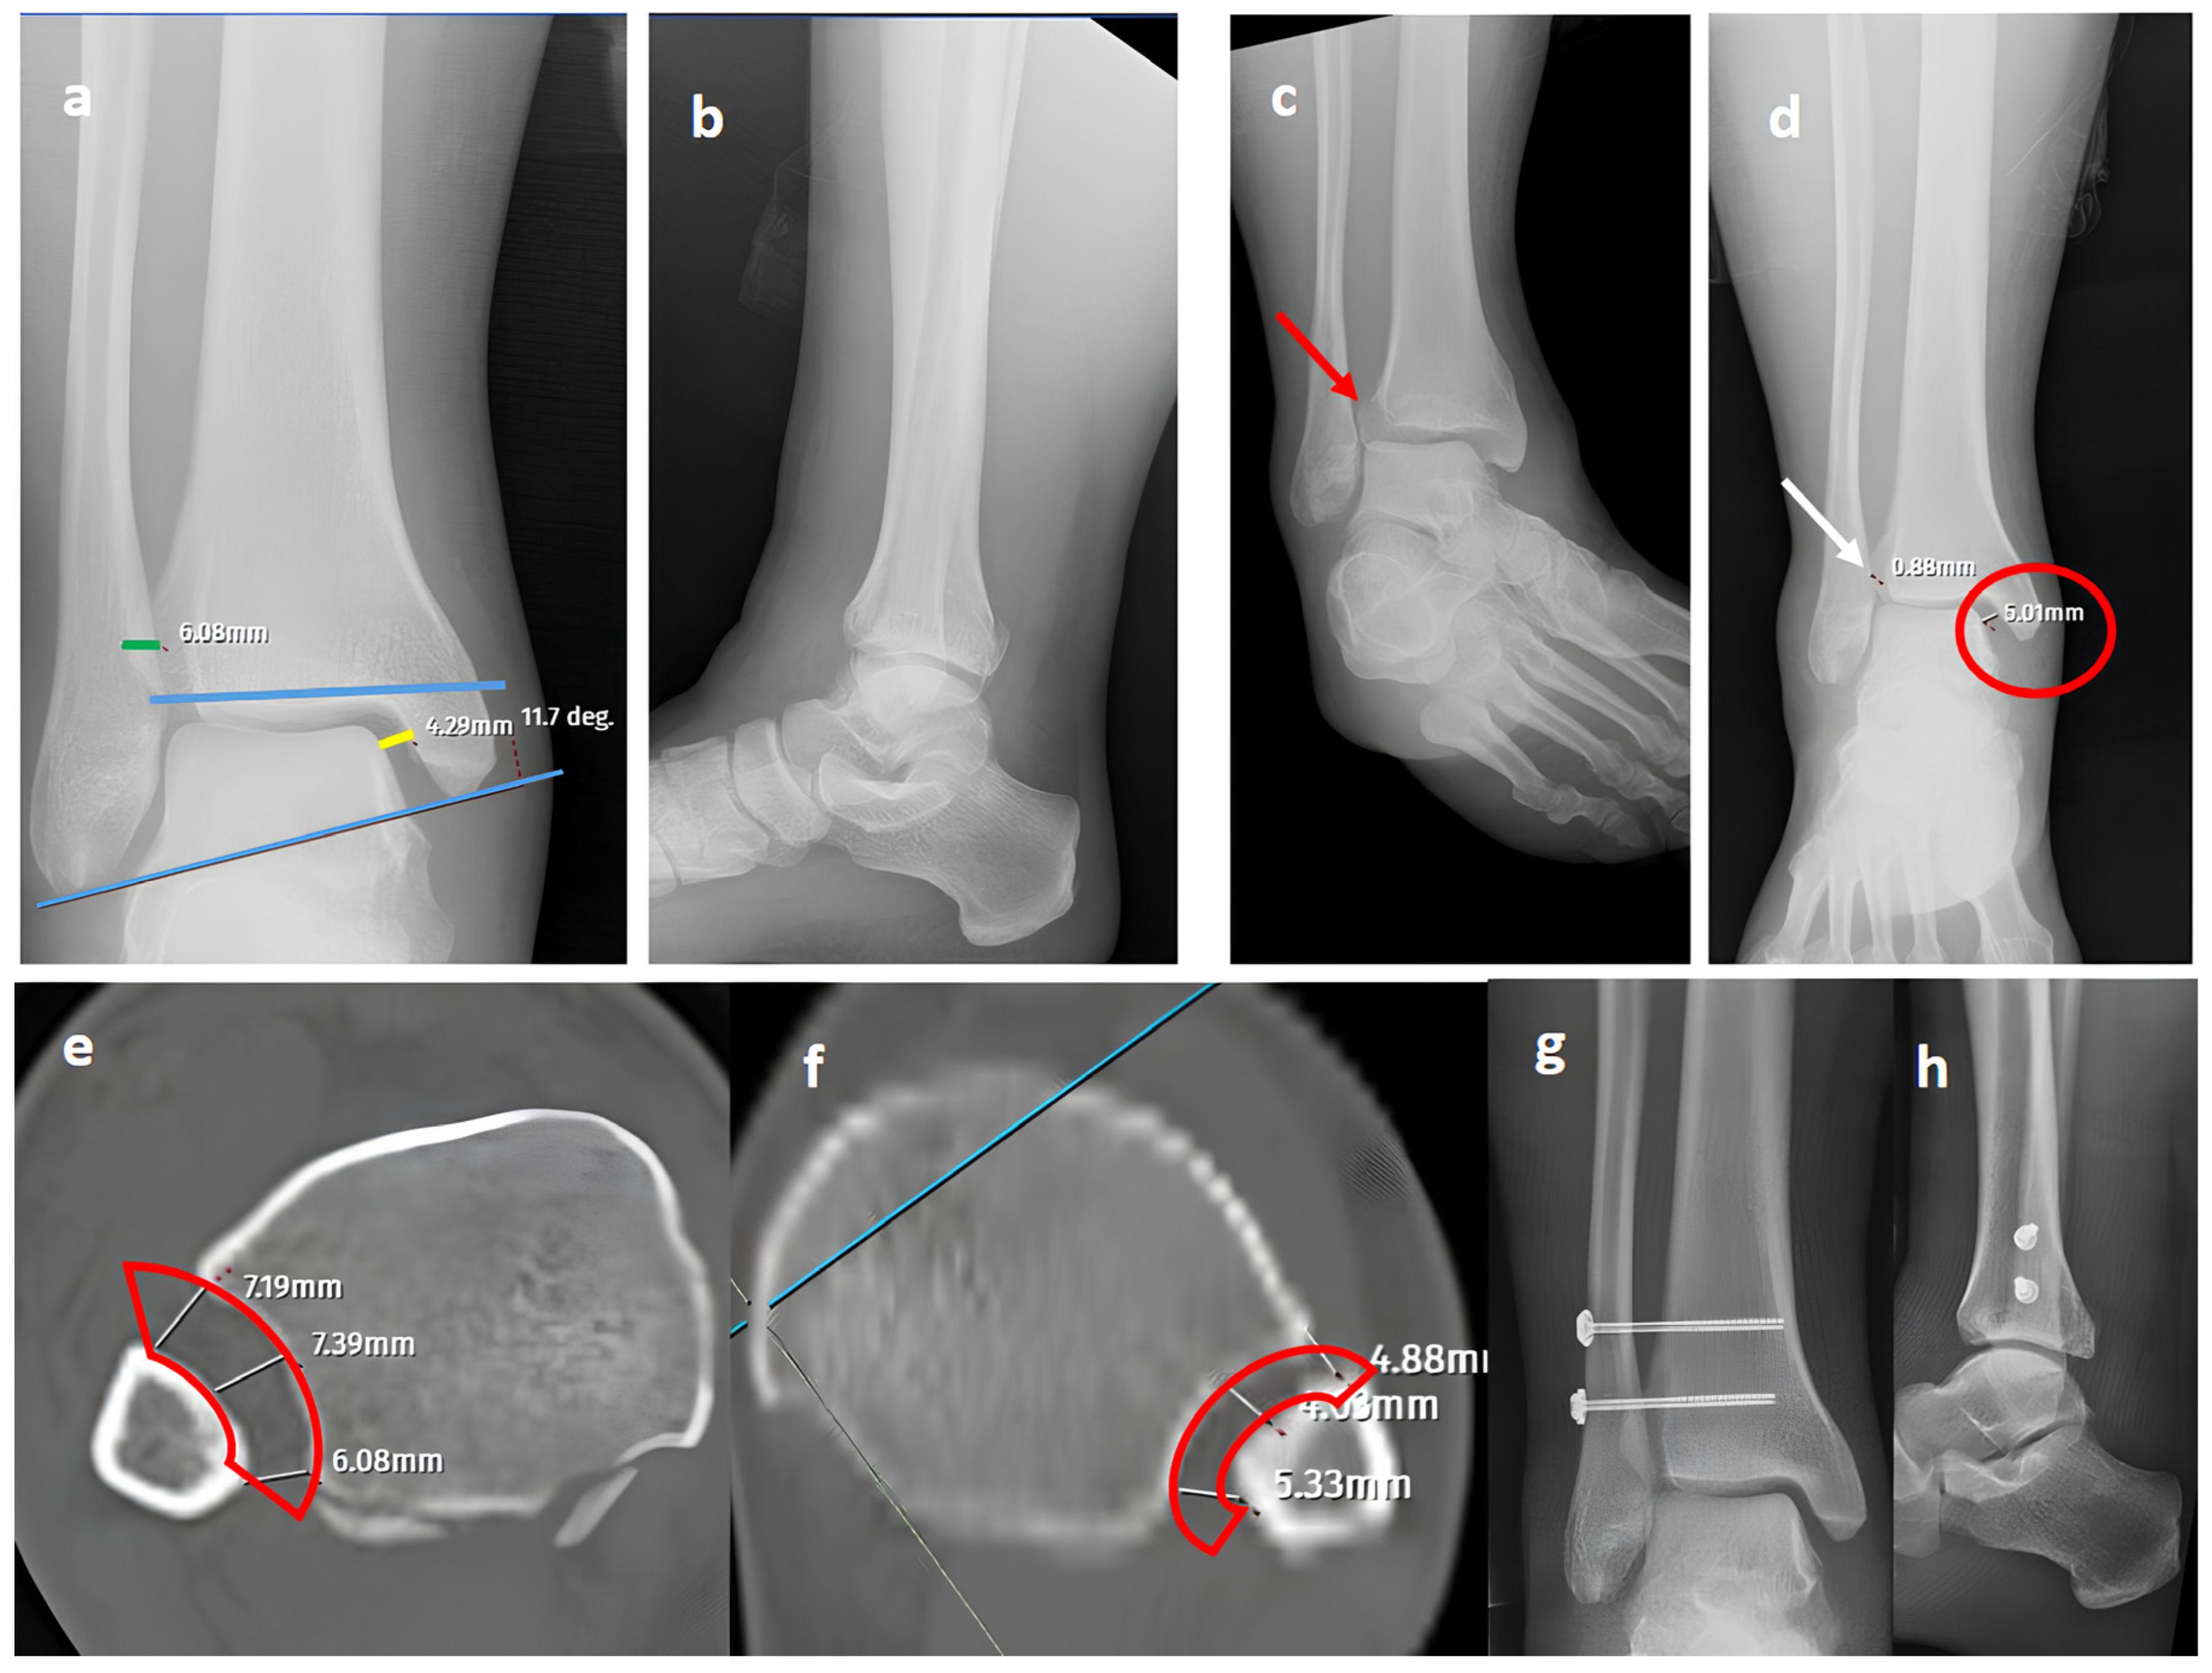

Figure 1. A trimalleolar right ankle fracture. (a,b) Standard AP and lateral views showing a bimalleolar fracture with a normal distal tibiofibular overlap (green line). (c) A mortise view showing an open distal tibiofibular distance (red arrow) indicating syndesmosis injury. (d) A GAASA view showing lateral displacement of the talus with a shift in the medial malleolus and distal fragment of the fibular segment. However, the proximal segment of the fibula is in place, indicating that the proximal syndesmosis is intact (yellow arrow). Axial CT images of the injured right ankle (e) and the uninjured left ankle (f) show measurement of the tibiofibular space (red block bow), which appears similar and within normal ranges, indicating an intact syndesmosis.

Figure 2. A Maisonneuve (pronation-external rotation IV) fracture. (a,b) Standard AP and lateral views showing a posterior malleolar fracture with a normal distal tibiofibular (green line) overlap, medial clear space (yellow line), and talocrural angle (blue lines). (c) A mortise view showing an obviously widened distal tibiofibular distance (red arrow), indicating syndesmosis injury. (d) A GAASA view showing lateral displacement of the talus with widening of the medial clear space (red circle) within physiological limits, indicating that the deltoid ligament is intact. However, widening is still evident for the distal tibiofibular distance due to syndesmosis injury (white arrow). (e) A comparison of axial CT images of the injured right ankle and axial CT images of the uninjured left ankle (f) reveals obvious distortion of the whole syndesmosis (red block bows) for the right side. (g,h) Postoperative X-rays showing reduction and fixation of the mortise without the need for the intervention of posterior structures, indicating that the deltoid ligament is intact, consistent with the GAASA image.

In our series, 19 of 36 SER type II and IV cases did not involve syndesmotic injury (Figure 1), which is consistent with the idea that medial and lateral injuries must be carefully assessed before surgical stabilization. These findings highlight that GAASA imaging is particularly reliable in PER injuries, where all medial and lateral structures are disrupted and the fibula is extensively fractured. In such cases, gravitational force causes the talus to exert downward pressure on the distal fibular fragment, producing clear widening of the medial clear space and distal tibiofibular joint [28]. Maisonneuve injuries, not classified by the Lauge-Hansen system, are inherently unstable and require surgical syndesmosis stabilization [29]. In our study, three cases had clear distal tibiofibular widening without pathological medial clear space widening (Figure 2). This contrasts with the cadaveric study by Krahnebühl et al., which reported that stress radiographs are reliable only when deltoid and syndesmotic injuries coexist, but are ineffective for isolated syndesmosis injuries [5]. Our findings suggest that even when the medial malleolus and deltoid ligament remain intact, gravitational force alone can cause lateral fibular displacement, resulting in decreased tibiofibular overlap.